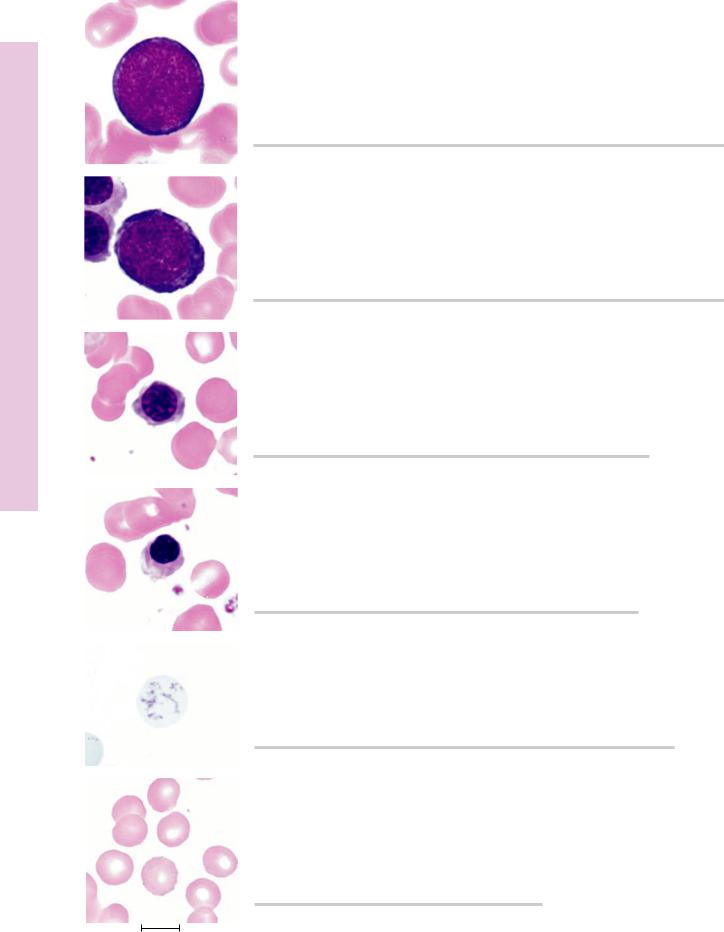

FIGURE 1. Myeloblast. Human bone marrow smear. ×1,325.

FIGURE 2. Promyelocyte. Human bone marrow smear. ×1,325.

ytopoiesis Granuloc• 6-5 PLATE

FIGURE 3a. Eosinophilic myelocyte. Human bone marrow smear. ×1,325.

FIGURE 4a. Eosinophilic metamyelocyte. Human bone marrow smear. ×1,325.

FIGURE 5a. Eosinophilic stab cell. Human bone marrow smear. ×1,325.

FIGURE 3b. Neutrophilic myelocyte. Human bone marrow smear. ×1,325.

FIGURE 4b. Neutrophilic metamyelocyte. Human bone marrow smear.

×1,325.

FIGURE 5b. Neutrophilic stab cell. Human bone marrow smear. ×1,325.

FIGURE 6. Neutrophil. Human bone marrow smear. ×1,325.

1.15 cm = 7.5 µm